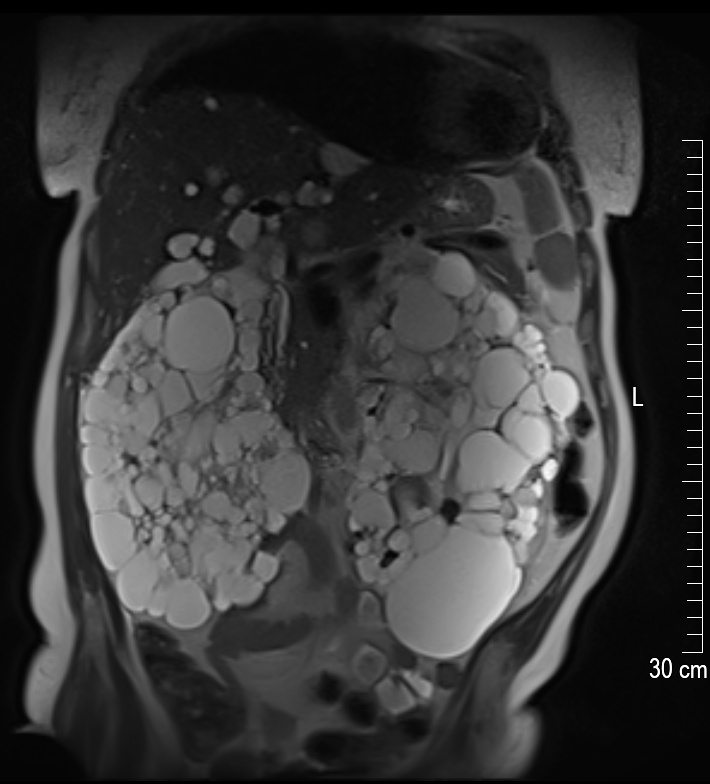

Die linke Niere ist circa 25 cm lang. Der große weiße Fleck unten ist eine der größten Zysten mit einer Länge von circa 8 cm. Die Niere ist so voluminös, dass sie eine richtige Beule ausformt. Die ist tatsächlich an meinem Körper sicht- und spürbar! In der rechten Niere befinden sich kleinere Zysten, dafür – so sieht es auf dem Bild aus – viel mehr als in der linken Niere. Alle anderen inneren Organe müssen den Nieren weichen – was mittlerweile zu starken Magenproblemen und teilweise auch Atemnot führt.

Es führt kein Weg mehr daran vorbei: Ich muss die linke Niere operativ entfernen lassen. Um Platz zu machen für ein mögliches Spenderorgan. Und um meinen Körper allgemein etwas zu entlasten.